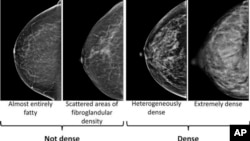

This image provided by the UW/Fred Hutch Cancer Center Breast Imaging in October 2024 shows mammogram scans with dense and not dense tissue.

Doctors who review mammograms have a system for classifying breast density.

There are four categories. The least dense category means the breasts are almost all fatty tissue. The most dense category means the breasts are mostly glandular and fibrous tissue.

Breasts are considered dense in two of the four categories: "heterogeneously dense" or "extremely dense." The other two categories are considered not dense.